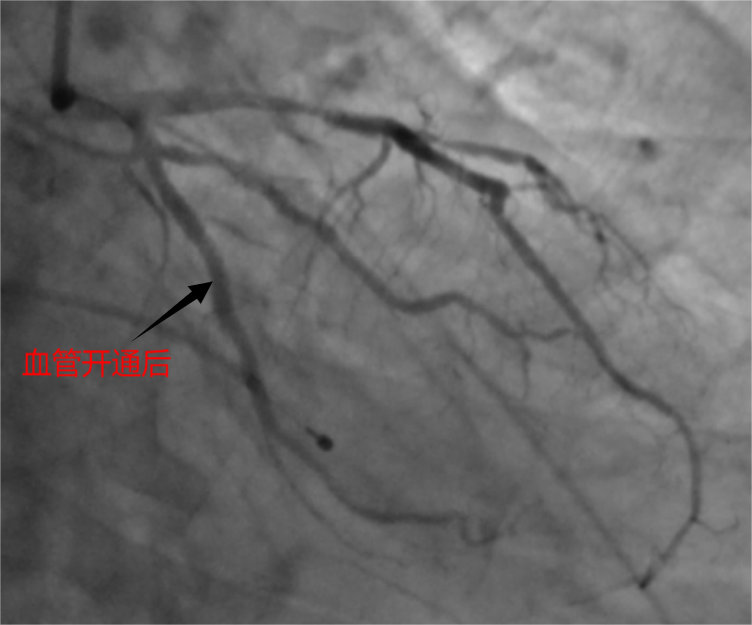

介入中,徐先增团队查出,杨先生的急性心肌梗塞由回旋支中段闭塞引起,于14时11分成功将血管重新开通,并为其植入一枚支架。从患者到达医院到血管开通,仅用时31分钟,远低于抢救标准所要求的90分钟,刷新了医院救治急性心肌梗死血管开通时间记录。术后复查造影显示,支架贴壁良好,无残留狭窄,杨先生生命体征平稳,胸痛症状消失。

14时11分成功将血管重新开通